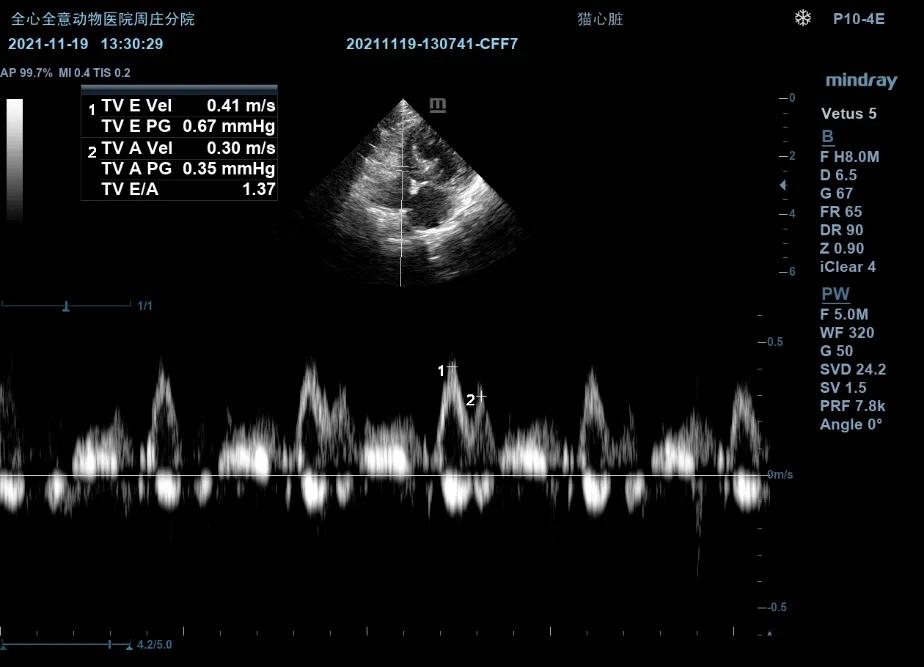

超声检查:

左侧心尖四腔(color):

可见收缩期二间瓣反流信号。

MR Vmax:4.07m/s